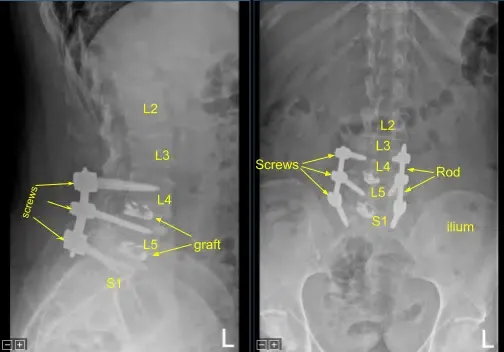

Las imágenes mostraron un mal funcionamiento y una colocación subóptima del tornillo del pedículo sacro derecho. Se recomendó una cirugía para descomprimir la raíz nerviosa lumbar que está siendo presionada por el tornillo pedicular y estabilizar la columna lumbar.

Se obtuvo una tomografía computarizada intraoperatoria, los datos se transfirieron al ordenador de neuronavegación y se verificó la precisión. Se utilizaron técnicas de neuronavegación para canular el primer segmento sacro derecho que luego se palpaba en busca de rupturas y se medía a una profundidad de 35 mm. Se utilizaba un tapón de 6,0 mm para enhebrar la canulación. De nuevo se palpó para detectar brechas y se colocó un tornillo pedicular de titanio de 7,5 x 35 mm con buen sujeito óseo y firmeza.

A continuación, se volvió a colocar el drapado al paciente y se realizó una segunda tomografía computarizada intraoperatoria que mostró la correcta posición de este tornillo pedicular. Las señales de neuromonitorización se mantuvieron estables en todo momento. A continuación, el proceso transversal L5-S1 y ala fueron decorificados con un taladro de alta velocidad para la artrodesis tras explorar la fusión y no identificar la artrodesis ósea ni el injerto óseo.

De nuevo, se colocó una varilla de titanio precortada precortada sobre los tulipanes de tornillo pedículo desde L4 hasta S1 y se aseguró con las tapas de bloqueo, que se apretaron con un dispositivo de par y antitorque. Se colocó un aloinjerto óseo morcelizado en L5-S1 en el lado derecho para la artrodesis.

La pequeña dehiscencia en la incisión del lado izquierdo fue desbridada y la piel se volvió a cerrar. Todas las incisiones se limpiaron y secaron de forma estéril, y los apósitos se aplicaron de forma estéril. Se aplicó un recipiente Hemovac con succión. La unidad C-arm se cubría de forma estéril y se utilizaba para la confirmación por AP y fluoroscopia lateral del correcto hardware y la posición de la instrumentación, específicamente la colocación de las varillas.